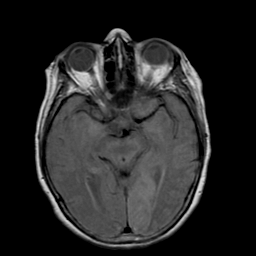

Stroke: proton density-weighted MR #2 -- Slice #10

[Home][Help][Clinical] Slice 10